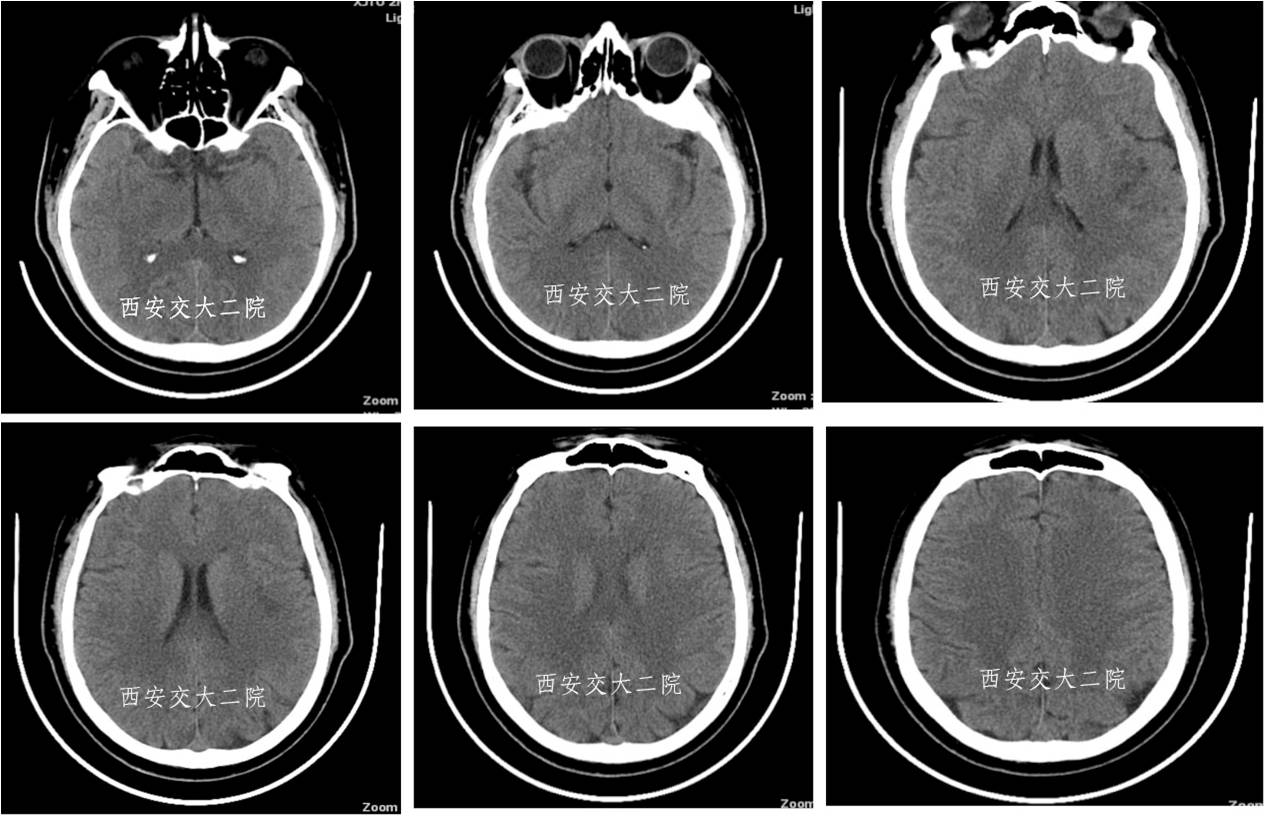

急诊脑CT

初步诊断

1. 脑栓塞 (左侧大脑中动脉闭塞)?

2. 冠心病

慢快综合征 心房纤颤

永久起搏器安置术后 心功能III级

3. 肺部感染

4. 2型糖尿病

病后2小时DSA示左颈内动脉眼段闭塞。